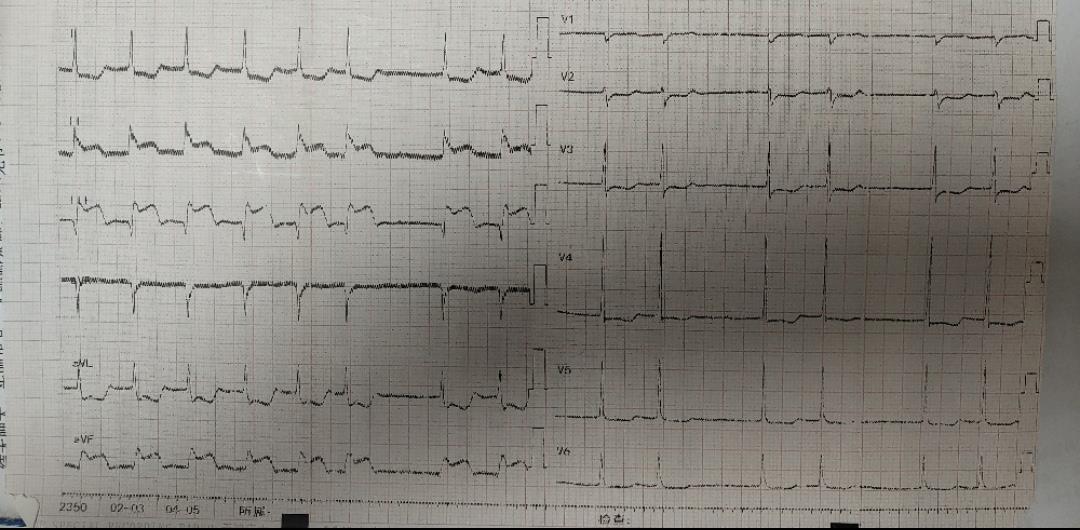

患者系102岁的超高龄女性,突发胸闷,伴大汗、乏力。外院就诊行心电图检查提示“心房颤动,II、III、AVF导联ST段显著抬高”,诊断急性下壁心肌梗死。由于患者体质差,年龄大等因素,当地医院转入我院,该患者合并房颤、血压低、精神差、症状重,生命危在旦夕,为救治患者,我院胸痛中心迅速启动导管室绿色通道,急诊行冠脉介入治疗。![]() 患者入介入室时已存在早期休克表现,脉搏微弱,桡动脉穿刺难度大,急诊备班的易主任凭借丰富的经验和高超的桡动脉穿刺技术,迅速为患者成功植入了桡动脉鞘管,并小心通过上肢扭曲的动脉顺利完成造影。经造影提示患者前降支开口闭塞,右冠脉开口闭塞,回旋支中段后闭塞,目前该患者仅有单支血管供血,心脏搏动微弱,随时可能发生死亡。易勇副主任争分夺秒,极短时间内顺利开通此次罪犯血管右冠脉,但植入支架后出现明显慢血流的情况,经给予硝普钠及反复冠脉抽吸处理后,患者血流恢复,成功完成手术。